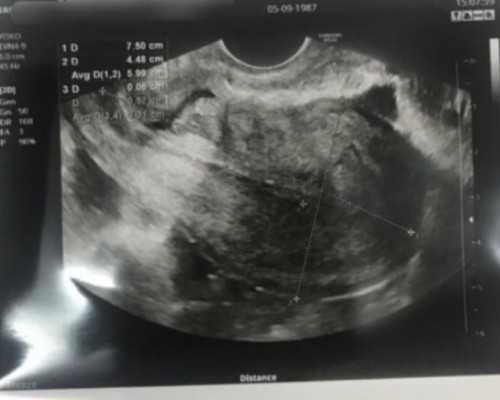

监测卵泡:

为评价卵巢刺激效果与决定取卵时间,须利用阴道B超来监测卵泡大小,并配合抽血检查血清激素,调整用药量。当二至三个以上的卵泡直径大于1。8cm,且1。4cm以上的卵泡数与血清雌激素水平相当时,便可注射人绒毛膜促性腺激素(hCG),促使卵泡成熟。在注射hCG后34-36小时取卵。